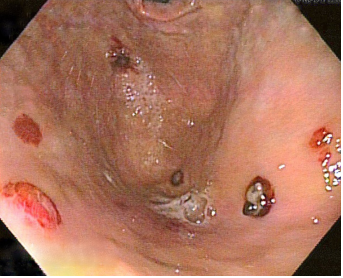

Gastroenterología lleva a nueva enteroscopia con balón anterógrada y retrograda, encontrando “innumerables lesiones nodulares sésiles eritemato-violáceas en estómago, duodeno, yeyuno, íleon y colon” (Figuras 1 a 3). Las biopsias tomadas de duodeno y estómago muestran “lámina propia infiltrada por células anaplásicas de tamaño variable, con figuras mitóticas abundantes y nucleolos prominentes, sin células en anillo de sello”, con lo que hacen diagnóstico de tumor maligno de origen linfoide versus sarcoma. Las pruebas para Herpes Virus Humano 8 (HHV8), herpes simple (HSV) 1 y 2, y citomegalovirus (CMV) fueron negativas en las células neoplásicas. En la citometría de flujo había disminución relativa de linfocitos T CD4 respecto a T CD8, sin expresión aberrante de linfocitos, y en la inmunohistoquímica, CK coctel negativa, CD30 positiva focal, CD31 positiva difusa, vimentina positiva difusa, con KI67 con índice de proliferación del 67 %, resto de panel de coloraciones especiales fueron negativas. El informe final inmunohistopatológico confirmó angiosarcoma intestinal.

Figura 3. Lesiones por angiosarcoma en colon con sangrado reciente que obstruye la correcta visualización.